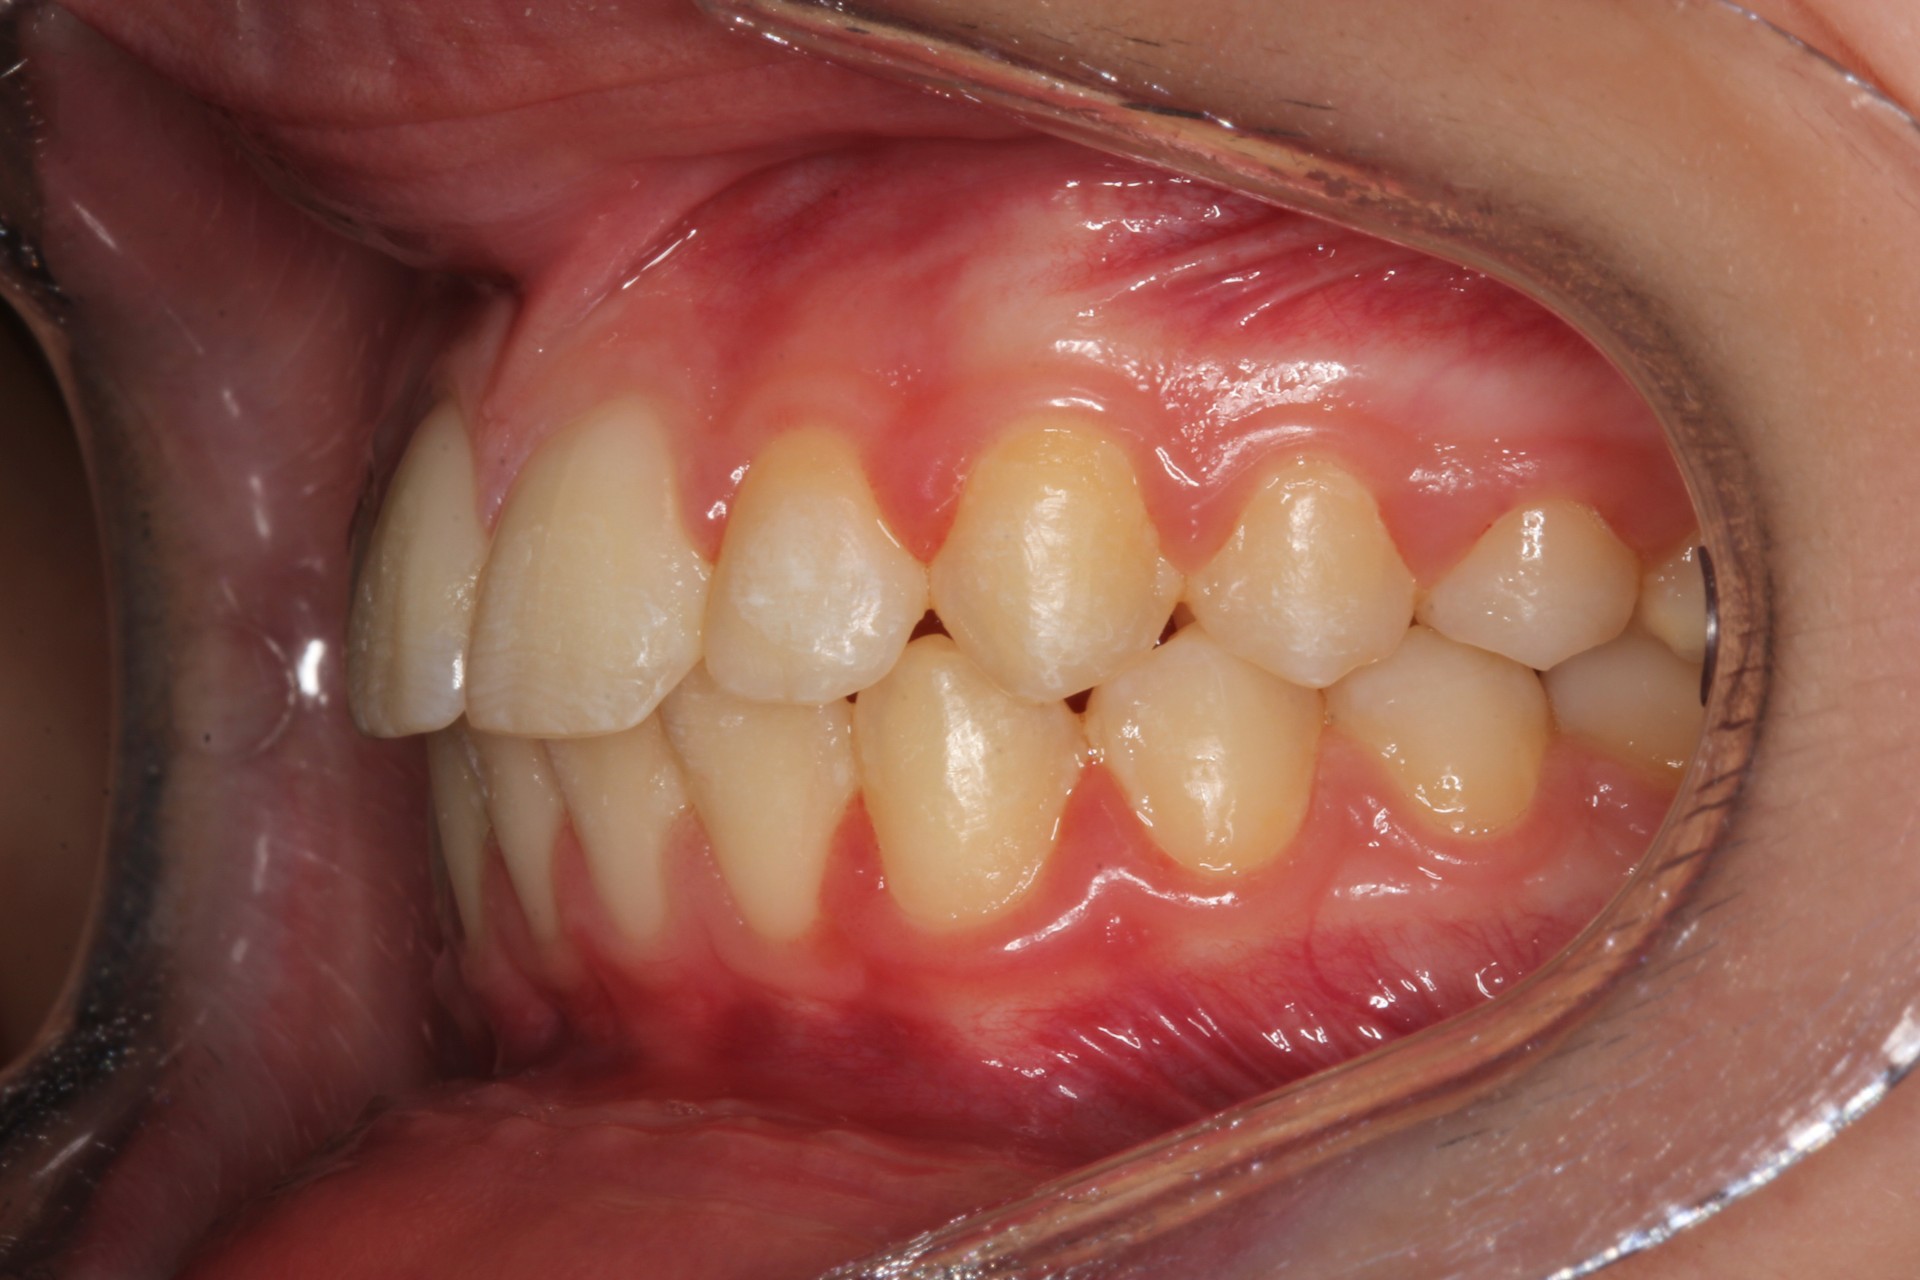

Protruding front teeth – Child case